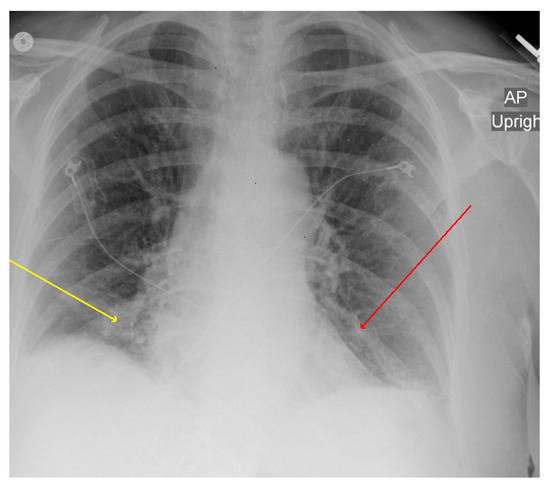

| Patient from this report | 78 | F | USA 2020 | Cough Hypoxia | Bilateral infiltrates and bilateral pleural effusion | DOX (21) | Yes | Improved |